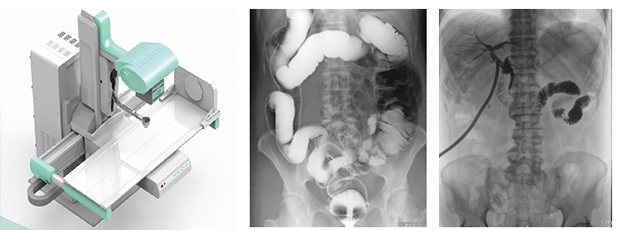

隨著現代醫療技術快速發展,傳統的X射線技術實現數字化,出現了多功能DR。多功能DR采用數字影像平板探測器取代傳統膠片,直接捕獲X線影像,并轉化為高清晰數字圖像,對比傳統的間接影像設備,多功能DR可以直接將X射線轉化成圖像,成像更清晰,放射劑量更小。

多功能DR大大提高了普通放射設備準確診斷的能力,為臨床創造了價值,它可以進行全身各部位的拍片、透視和點片攝影。接下來小編給大家介紹一下這三種模式的區別。

拍片攝影是利用X線穿過人體被檢查部位并感光在膠片上形成影像而進行診斷的方法,它有膠片可供長時間觀看分析,便于診斷分析及會診讀片、資料存儲。另外,由于曝光時間很短,人體受到的輻射比透視小得多。但是當某處有疑點時無法轉動體位從不同角度觀察,無法看全貌。

透視是用X線穿過人體被檢查部位在熒光屏上顯示的影像而進行診斷的方法,連續出射線(攝影),在檢查時可以轉動病人的身體,從各種不同的位置和角度來觀察病變的狀況,也可以觀察器官的運動功能,能夠立即得到檢查結果,進行介入性的操作等。但是因為透視會持續輸出射線,病人接受的輻射劑量較大,并且透視對細微病變和厚實部位觀察不太清楚,不能留下長久性的記錄。

點片攝影是在透視的條件下,對病變部位進行可視化觀察,待發現疑似病變部位的時候進行瞬間點片,從而能夠準確獲取病變部位的高清影像用于臨床診斷,從而在一定程度上降低漏診誤診率。病人不動,通過選擇鍵由透視直接切換攝影的曝光過程。在透視過程中,保存一幅靜止的圖像。常用于消化道、膽系造影下的攝影等。它既可以觀察運動器官的運動功能,又能在有感興趣的圖像時,對膠片曝光保留感興趣的圖像,便于進一步診斷。